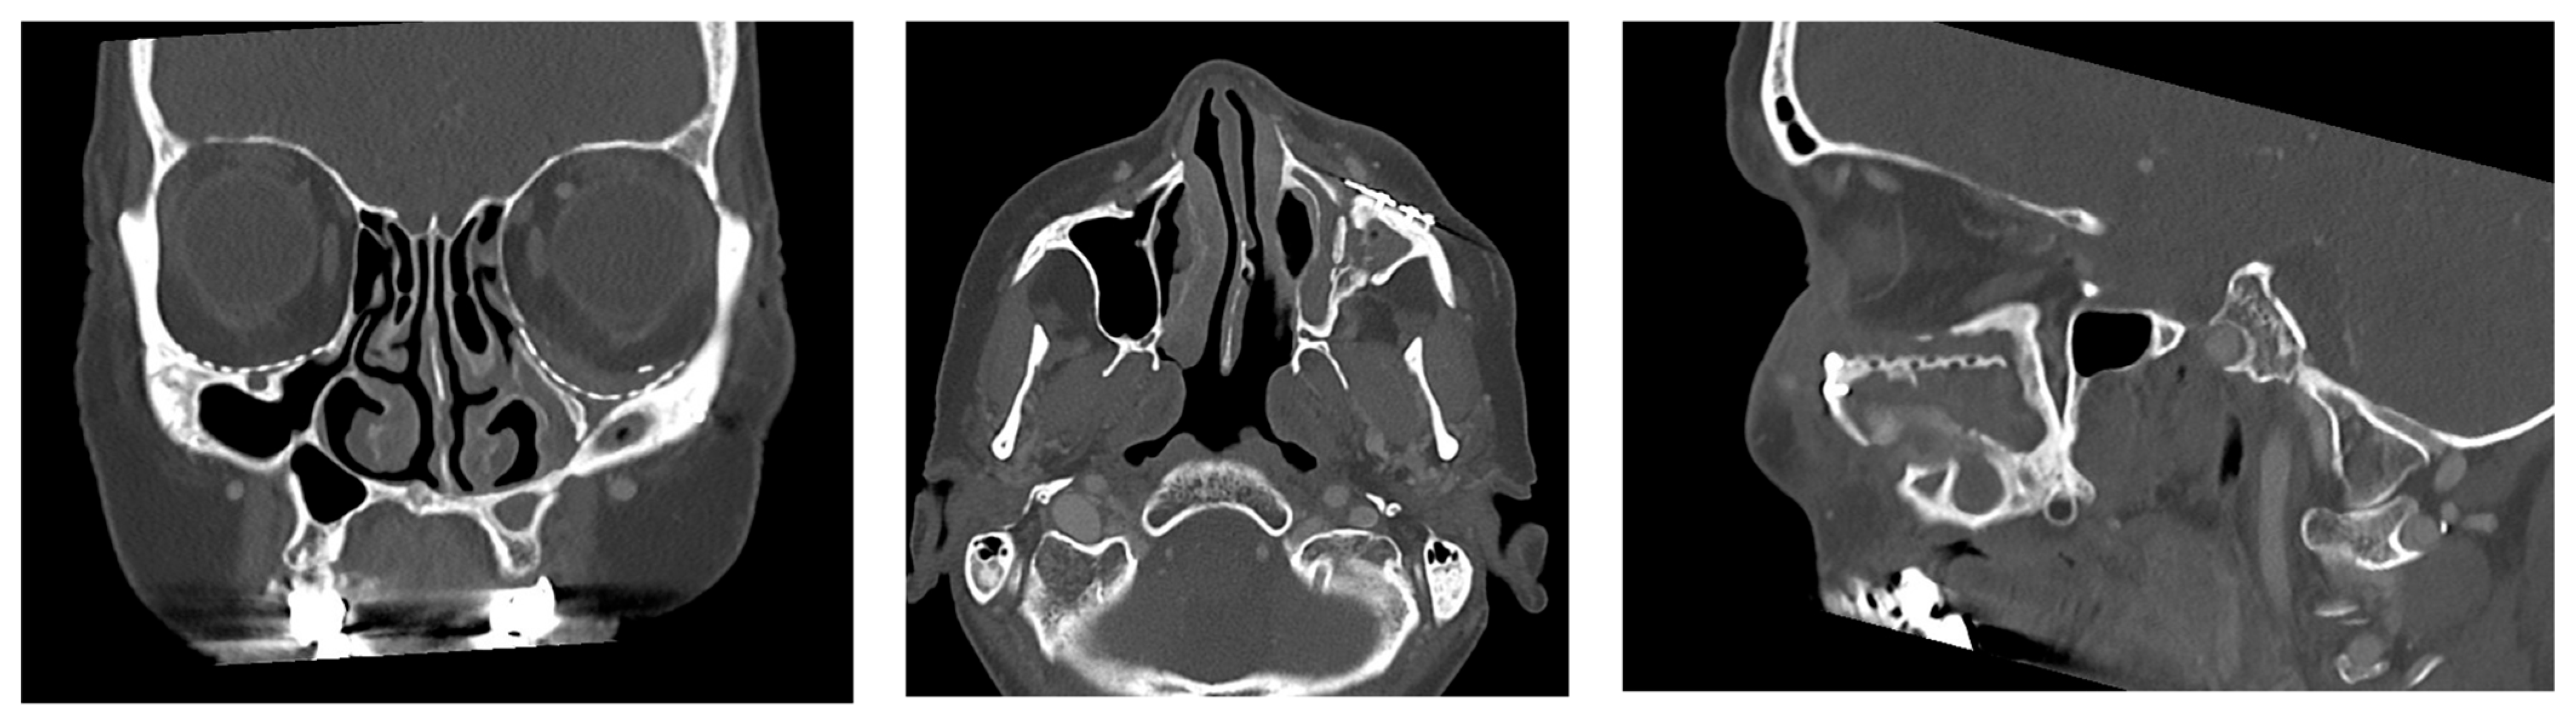

- Patent ostium of the maxillary sinus (coronal plane)

- Non-inflammatory PNSs (three planes)

- Exposure of the osteosynthesis screws (axial and sagittal planes)

- Exposure of the PSI to the maxillary sinus (coronal and sagittal planes)

- Remodeling of the fractured orbital walls and bone apposition at the PSI indicating osseointegration (three planes)

- Exposure of the fixation screws (infraorbital recess of the maxillary sinus) and limited exposure of the PSI (transition zone, ethmoid cells) without signs of mucosal swelling in these regions (n = 6 each)

- (Basal) mucosal swelling in the maxillary sinus indicative of chronic maxillary sinusitis, irrespective of the complexity of the primary injury (n = 4)

- Bone apposition at the PSI as a sign of osseointegration (n = 16)

- Remodeling of the dislocated bone fragments of the orbital walls (n = 16), including in the area of the infraorbital canal.